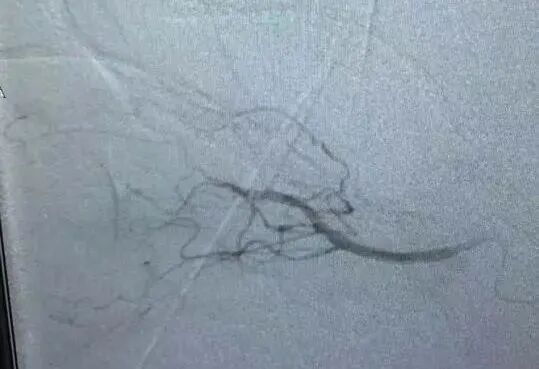

治療后DSA影像(頸內(nèi)動(dòng)脈、眼動(dòng)脈均恢復(fù)血供)

經(jīng)檢查,患者頸內(nèi)動(dòng)脈急性閉塞,斑塊脫落至眼動(dòng)脈遠(yuǎn)端,栓塞眼動(dòng)脈,情況十分危險(xiǎn)!經(jīng)過(guò)黃志勇主任醫(yī)師、景英朝主任醫(yī)師、李江副主任醫(yī)師等卒中專(zhuān)家的迅速評(píng)估后,果斷為患者進(jìn)行了介入手術(shù)治療,先開(kāi)通頸內(nèi)動(dòng)脈急性閉塞的血管,保證顱內(nèi)供血,然后通過(guò)溶栓治療,讓眼動(dòng)脈恢復(fù)供血,保證視力。目前,患者已病情穩(wěn)定。